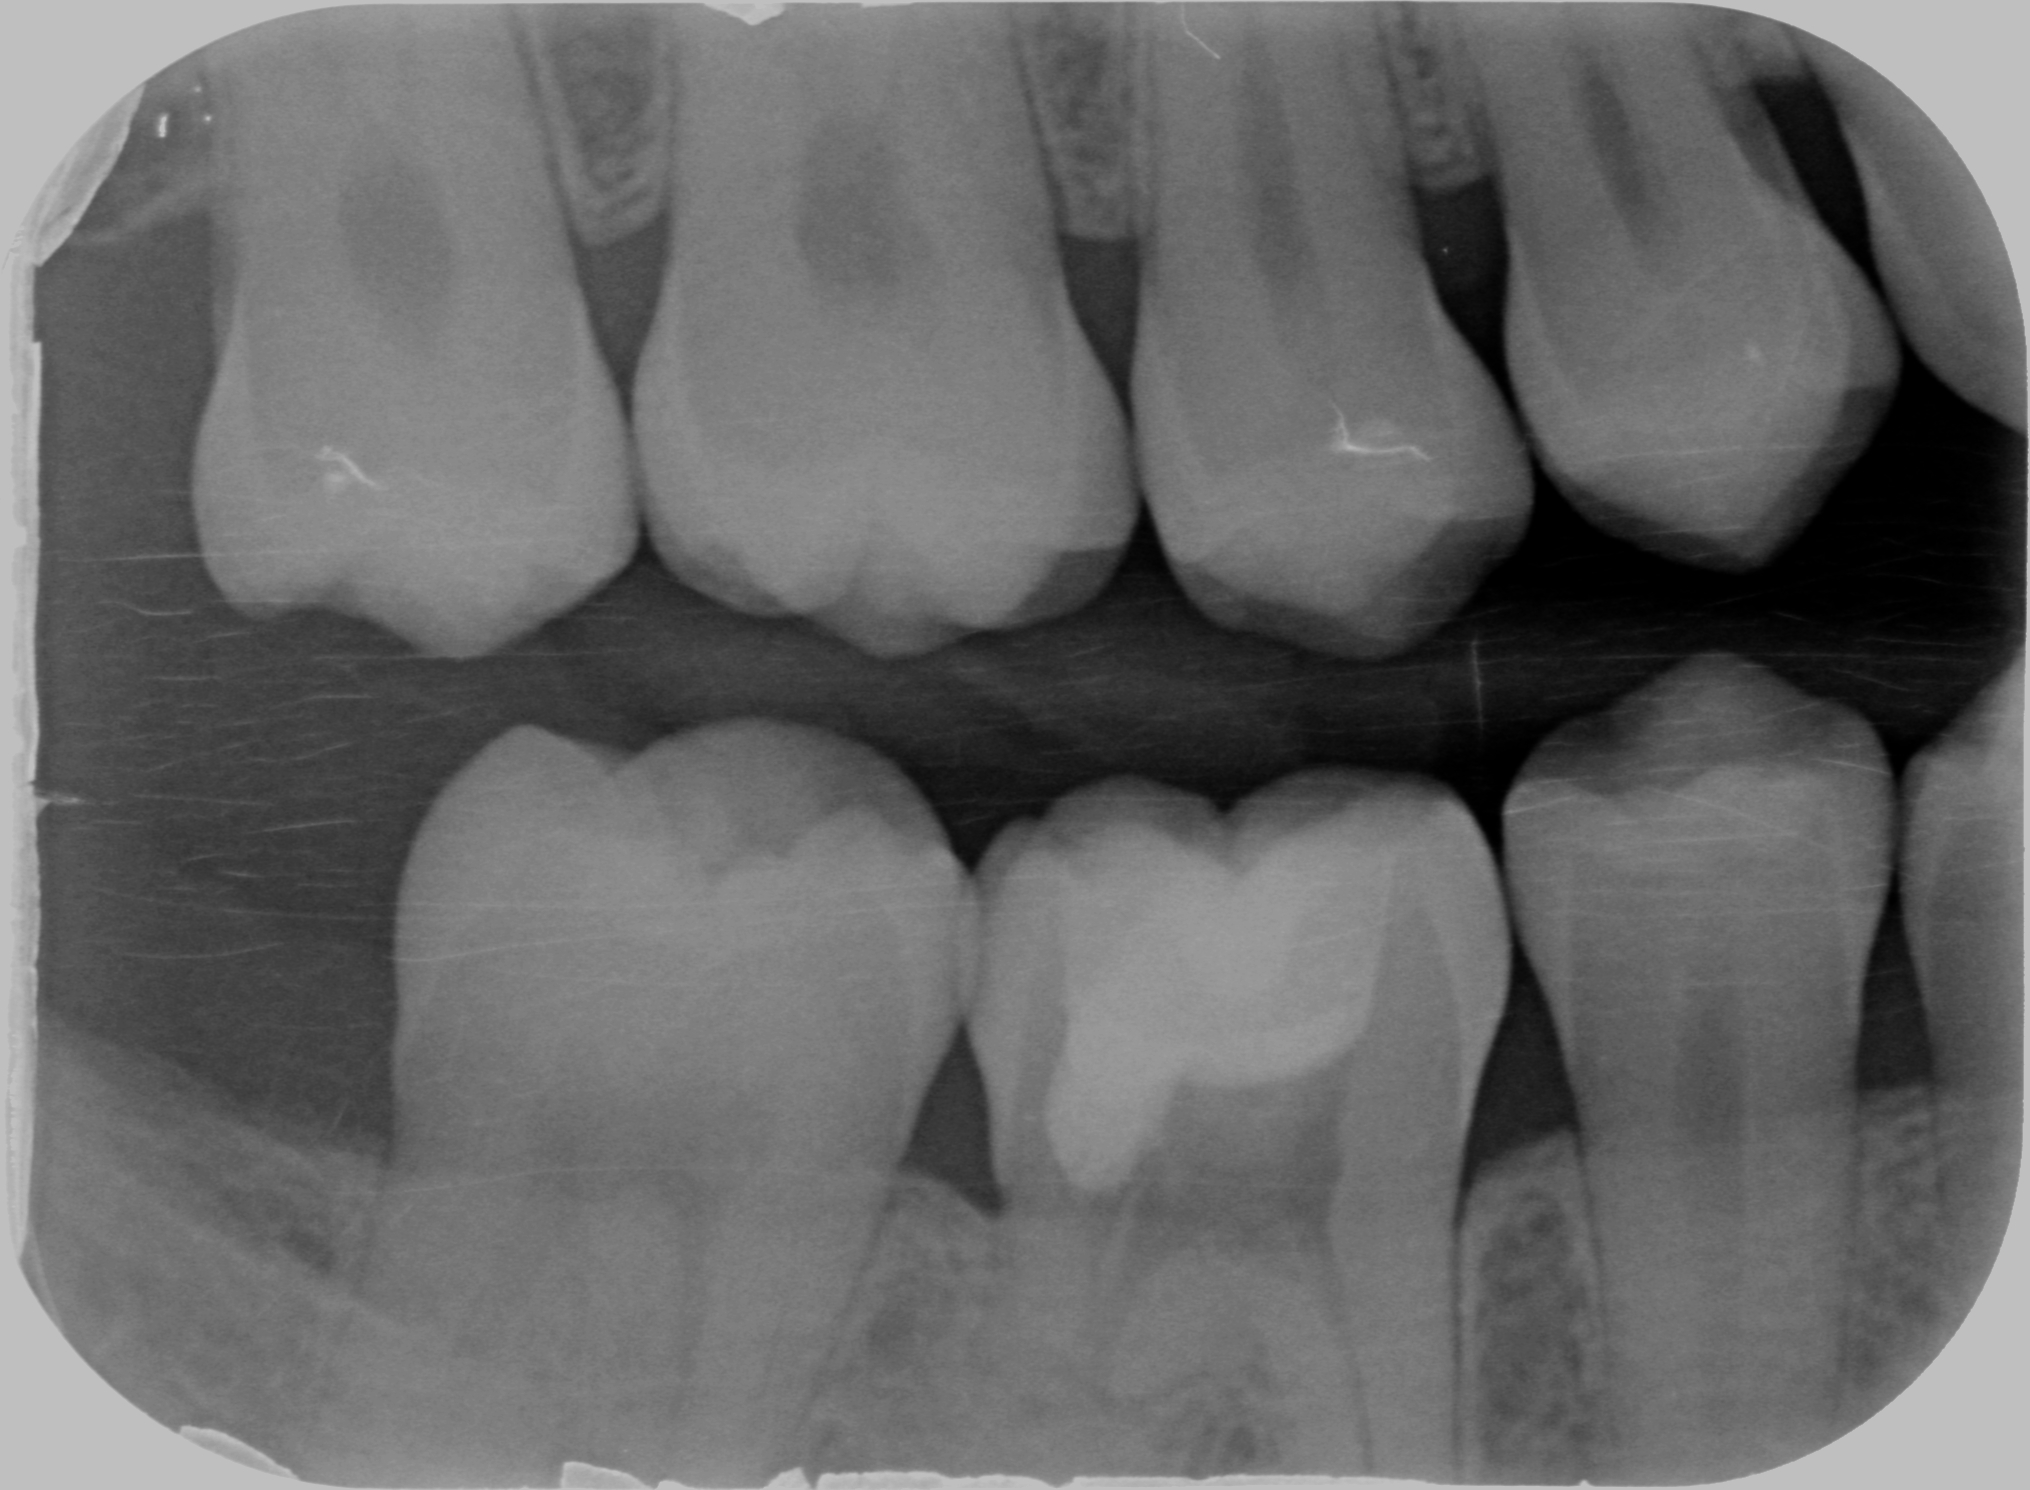

Nel 1999, infatti, Heithersay classifica i riassorbimenti in quattro classi (Heythersay, 1999):

- la classe 1 prevede un piccolo riassorbimento in zona cervicale con una superficiale penetrazione nella dentina;

- la classe 2 presenta un riassorbimento ben definito che penetra vicino alla camera pulsare con poca o nessuna estensione nella dentina radicolare;

- la classe 3 vede estendersi il riassorbimento al terzo coronale della radice;

- la classe 4 identifica i riassorbimenti estesi ed invasivi che si estendono oltre il terzo coronale della radice

La terapia prevede la rimozione del tessuto di granulazione per via ortograda o per via chirurgica e il riempimento del difetto con composito, come se fosse una otturazione, nel caso dei difetti di classe 1 e 2 (spesso si rende necessario associare questo a cura canalare e allungamento di corona clinica). Nei riassorbimenti esterni di classe 3 o 4 il difetto viene spesso riempito con MTA visto che spesso si verificano comunicazioni col parodonto (io ad oggi uso la Biodentine, ma questo sarà oggetto di un altro post).

Ooooook. Proprio quando ero pronto ad intervenire, questa volta sapendo cosa stavo facendo, leggo che Heithersay consigliava di non intervenire nei riassorbimenti esterni di classe 4 perché il successo che potevo attendermi era del 12,5%!!!! (Heithersay, 1999)

Ma guardando un dente in apparenza sano, che dava alla paziente, che era in corso di trattamento con apparecchio invisibile, solamente un senso di presenza, potevo pensare di estrarre il dente?

Allora per capirci qualcosa in più ho fatto una cone beam.